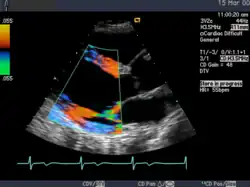

Die Sonografie ist das wichtigste Verfahren bei der Differentialdiagnose eines akuten Abdomens, bei Gallensteinen oder bei der Beurteilung von Gefäßen und deren Durchlässigkeit, vor allem an den Beinen. Weiterhin wird sie standardmäßig zur Untersuchung der Schilddrüse, des Herzens – dann Echokardiografie oder Ultraschallkardiografie (UKG) genannt –, der Nieren, der Harnwege und der Harnblase benutzt. Durch den Einsatz von Echokontrastverstärkern (Kontrastmittel) ist in geeigneten Fällen eine weitere Verbesserung der Diagnostik möglich.

Ihre Hauptanwendung findet diese Untersuchungsmethode in der Echokardiografie, um Bewegungen einzelner Herzmuskelbereiche und der Herzklappen genauer untersuchen zu können. Die zeitliche Auflösung dieses Modus ist bestimmt durch die maximale Wiederholrate der Schallimpulse und beträgt schon bei 20 cm Tiefe über 3 kHz.

Die Aussagekraft der Sonografie kann erheblich durch die Anwendung des Doppler-Effekts erhöht werden. Man unterscheidet eindimensionale Verfahren (Pulsed-Wave-Doppler, Continuous-Wave-Doppler, auch als D-mode bezeichnet) von zweidimensionalen, farbkodierten Anwendungen (Farbdoppler – F-mode). Die Kombination B-Bild mit Pulsed-Wave-Doppler (PW-Doppler) nennt man auch Duplex.[4]

Doppler-Verfahren werden benutzt zur Bestimmung von Blutfluss-Geschwindigkeiten, zur Entdeckung und Beurteilung von Herz(klappen)fehlern, Verengungen (Stenosen), Verschlüssen oder Kurzschlussverbindungen (Shunts), siehe Farbkodierte Doppler-Sonografie.

Bei der farbkodierten Doppler-Sonografie wird für einen großen Bereich eines konventionellen Ultraschallbildes (Color-Window) die örtliche Doppler-Frequenz (= mittlere Flussgeschwindigkeit) und deren Schwankungsbreite bestimmt. Damit möchte man die Turbulenz der Strömung abschätzen. Aufgrund der statistischen Bewegungen der Streuteilchen ist die Schwankungsbreite der Fließgeschwindigkeit jedoch stets größer als die Turbulenz. Das Ergebnis wird in Falschfarben auf dem B-Bild überlagert, also in Farbtönen von rot und blau für verschiedene Blutgeschwindigkeit und grün für Turbulenz. Hierbei steht üblicherweise die Farbe Rot für Bewegung auf den Schallkopf zu, während mit blauen Farbtönen Flüsse weg von der Sonde codiert werden. Bereiche der Geschwindigkeit 0 werden durch die Elektronik unterdrückt.

Anwendung des Doppler-Verfahrens bei einer Herzuntersuchung: Mitralklappeninsuffizienz

Anwendung des Doppler-Verfahrens bei einer Herzuntersuchung: Mitralklappeninsuffizienz -

Eine spezielle Anwendung ist der Gewebe-Doppler (auch Tissue-Doppler), bei dem nicht die Blutflussgeschwindigkeiten, sondern die Geschwindigkeit des Gewebes, insbesondere des Myokards gemessen und dargestellt werden. Gegenüber den herkömmlichen Doppler-Verfahren treten wesentlich geringere Frequenzverschiebungen auf, und daher erfordert diese Untersuchungsmethode besondere Gerätemodifikationen. Eine Anwendung des Gewebe-Dopplers sind Strain (Elastizität) und Strain Rate (Elastizitäts-Rate) Imaging: hier wird die Kontraktilität einzelner Gewebeabschnitte des Herzmuskels gemessen, womit man hofft, bessere Aussagen zur regionalen Wandbewegung machen zu können.[6]